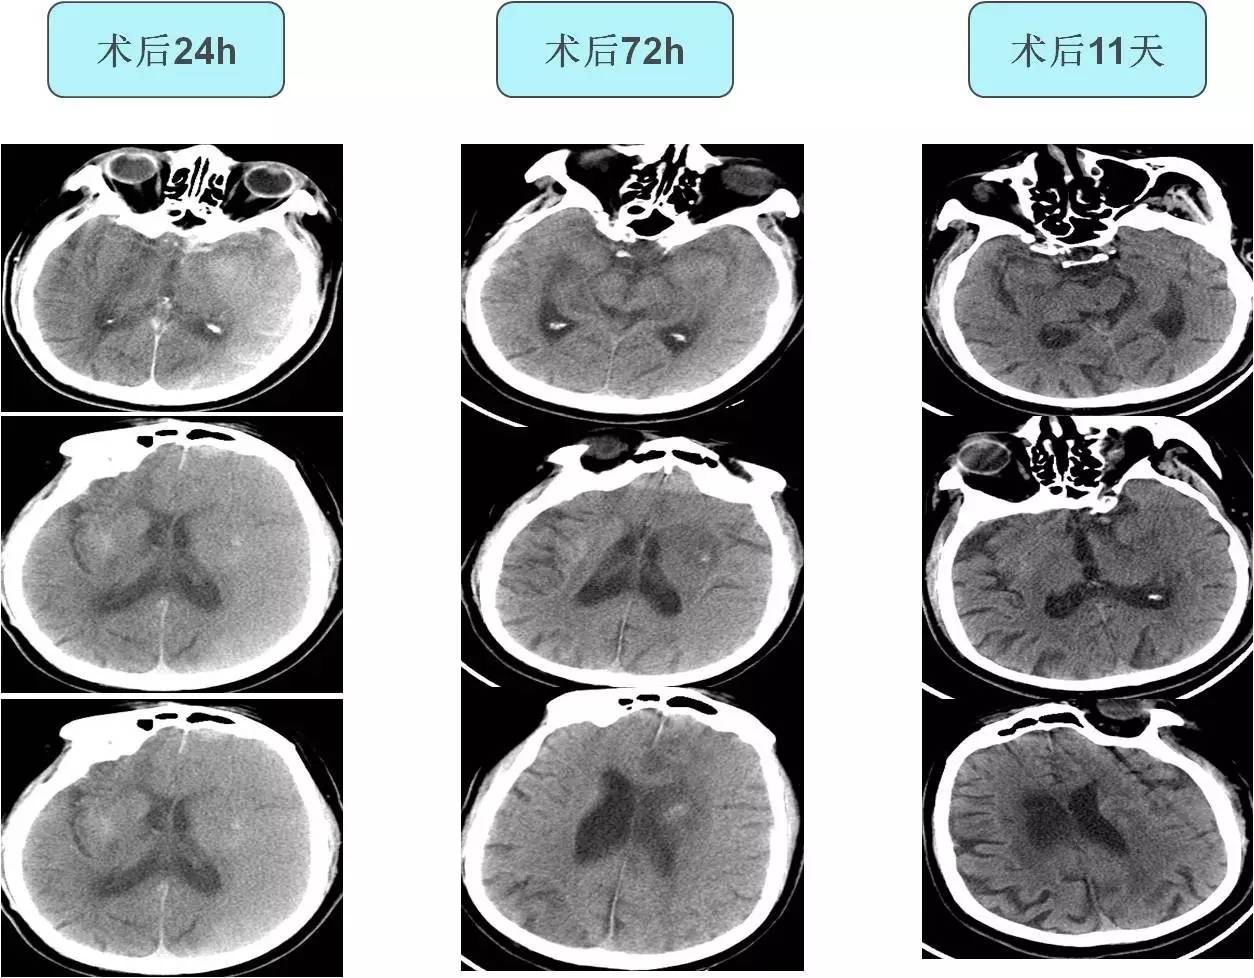

术后

》术后常规给予补液治疗,多巴胺持续泵入,维持血压。

》术后8h,患者血压逐渐升高,多巴胺减量、停用,改用乌拉地尔泵入,收缩压多位于160mmHg左右。

》术后10h出现发热,体温最高达38.8℃,无头痛,无恶心、呕吐,无肢体抽搐。查体:浅昏迷,双眼左侧凝视,右侧肢体肌张力低,疼痛刺激无反应,右侧巴氏征阳性。

诊断及治疗